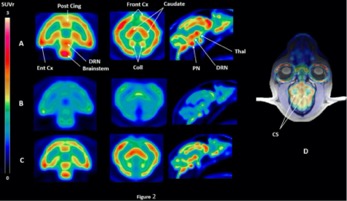

β Preclinical validation of [18F]2FNQ1P as a specific PET radiotracer of 5-HT6 receptors in rat, pig, non-human primate and human brain tissue

S. Emery, S. Fieux, B. Vidal, P. Courault, S. Bouvard, C. Tourvieille, T. Iecker, T. Billard, L. Zimmer, S. Lancelot

Nucl. Med. Biol. 2020, 82-83, 57-63.